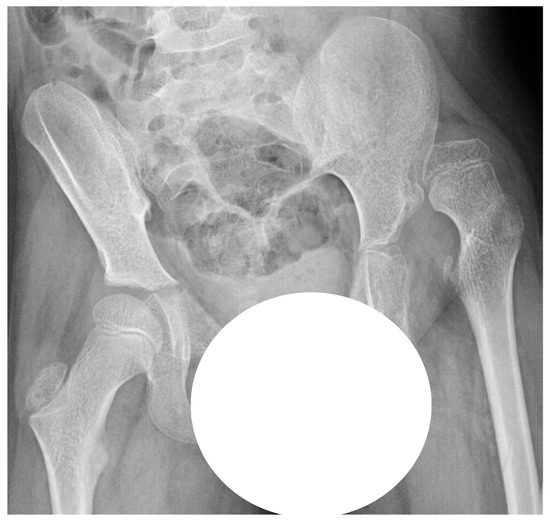

This was a retrospective registry study based on data from the CPUP and Statistics Sweden. In the CPUP, the gross motor function is classified by the internationally used Gross Motor Function Classification System (GMFCS); this system is a five-level scale in which level I represents the highest level and level V represents the lowest level of gross motor function [18,19]. All children up to 8 years of age within the GMFCS levels III–V are radiographically examined with a pelvic anteroposterior view annually and those within the GMFCS level II at 2 and 6 years of age. Children in level I are not examined radiographically provided that the child has a normal pain-free range of hip motion. After 8 years of age, the examination intervals are determined individually based on the results of previous examinations and clinical reports. The degree of displacement of the femoral head is measured with the Reimer’s Migration Percentage (MP), where MP 100% defines hip dislocation (Figure 2).

Figure 2. Measurement of hip migration percentage (MP). MP = a/b × 100.